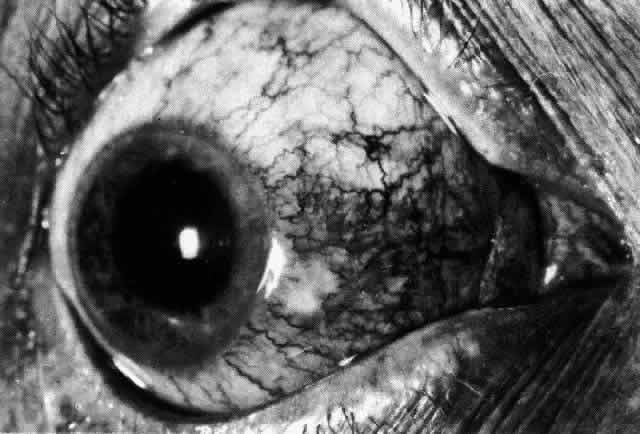

episcleritis and nodular episcleritis. ETIOLOGY Thirty percent of patients with episcleritis had some associated general conditions,6–8 but the rest defied all attempts to discover an etiology. Although some patients had a strong family history of atopy, results of patch and prick testing were uniformly negative. Of those in whom an etiology was found, only 5% showed any association with collagen disease, 7% had an association with herpes zoster, and 3% each had an association with gout or syphilis; the rest had associated conditions such as erythema nodosum, Schönlein-Henoch purpura, erythema multiforme, contact with industrial solvents, or penicillin sensitivity, indicating an immune basis for the condition. PATHOLOGY Microscopic and electron microscopic studies of biopsy specimens from patients with simple and nodular episcleritis have been totally noncontributory in the attempt to discover the etiology of this condition. The inflamed area is packed with lymphocytes and a few other inflammatory cells, but there are no mast cells, plasma cells, or eosinophils. CLINICAL MANIFESTATIONS The onset is usually acute; the eye may become red and painful in as short a time as half an hour. The patient's main complaint is redness of the eye, which is often sectorial and may be accompanied by a feeling of hotness, pricking, and mild discomfort. There is no discharge, although the eye waters occasionally. Pain may be absent, but the discomfort may be so severe that patients cannot pursue their normal occupation. The pain is localized to the eye, rarely radiating to the forehead and never producing the severe boring pain that is so commonly described in scleritis. In a severe attack the lids may become swollen, but this is a rare occurrence. If photophobia is present, an accompanying corneal condition should be suspected. Simple and nodular episcleritis differ in their clinical courses, but in both the edema and infiltration are entirely within the episcleral tissues. The sclera is not involved. The maximum congestion is in the superficial episcleral network, with some slight congestion of the conjunctival vessels and deep episcleral vessels (Fig. 10). The intraocular structures are not involved in either variety, nor is the visual acuity affected. Anterior segment fluorescein angiography reveals a normal vascular pattern but a very rapid flow rate, with the whole transit of the dye being completed within 2 or 3 seconds (Figs. 11 and 12).

The redness of simple episcleritis may be intense, varying from a fiery-red or a brick-red discoloration to a mild red flush, but it does not have the bluish tinge that is seen in scleritis. The distribution is usually sectorial but can involve the whole anterior segment of the globe. The episcleral vessels are engorged but retain their normal radial position and architecture (Figs. 13 and 14; Color Plate 1A). In simple episcleritis, there is a diffuse edema of the episcleral tissues. These tissues are sometimes infiltrated with gray deposits that appear yellow in red-free light. Surprisingly, the eye is rarely tender to the touch.